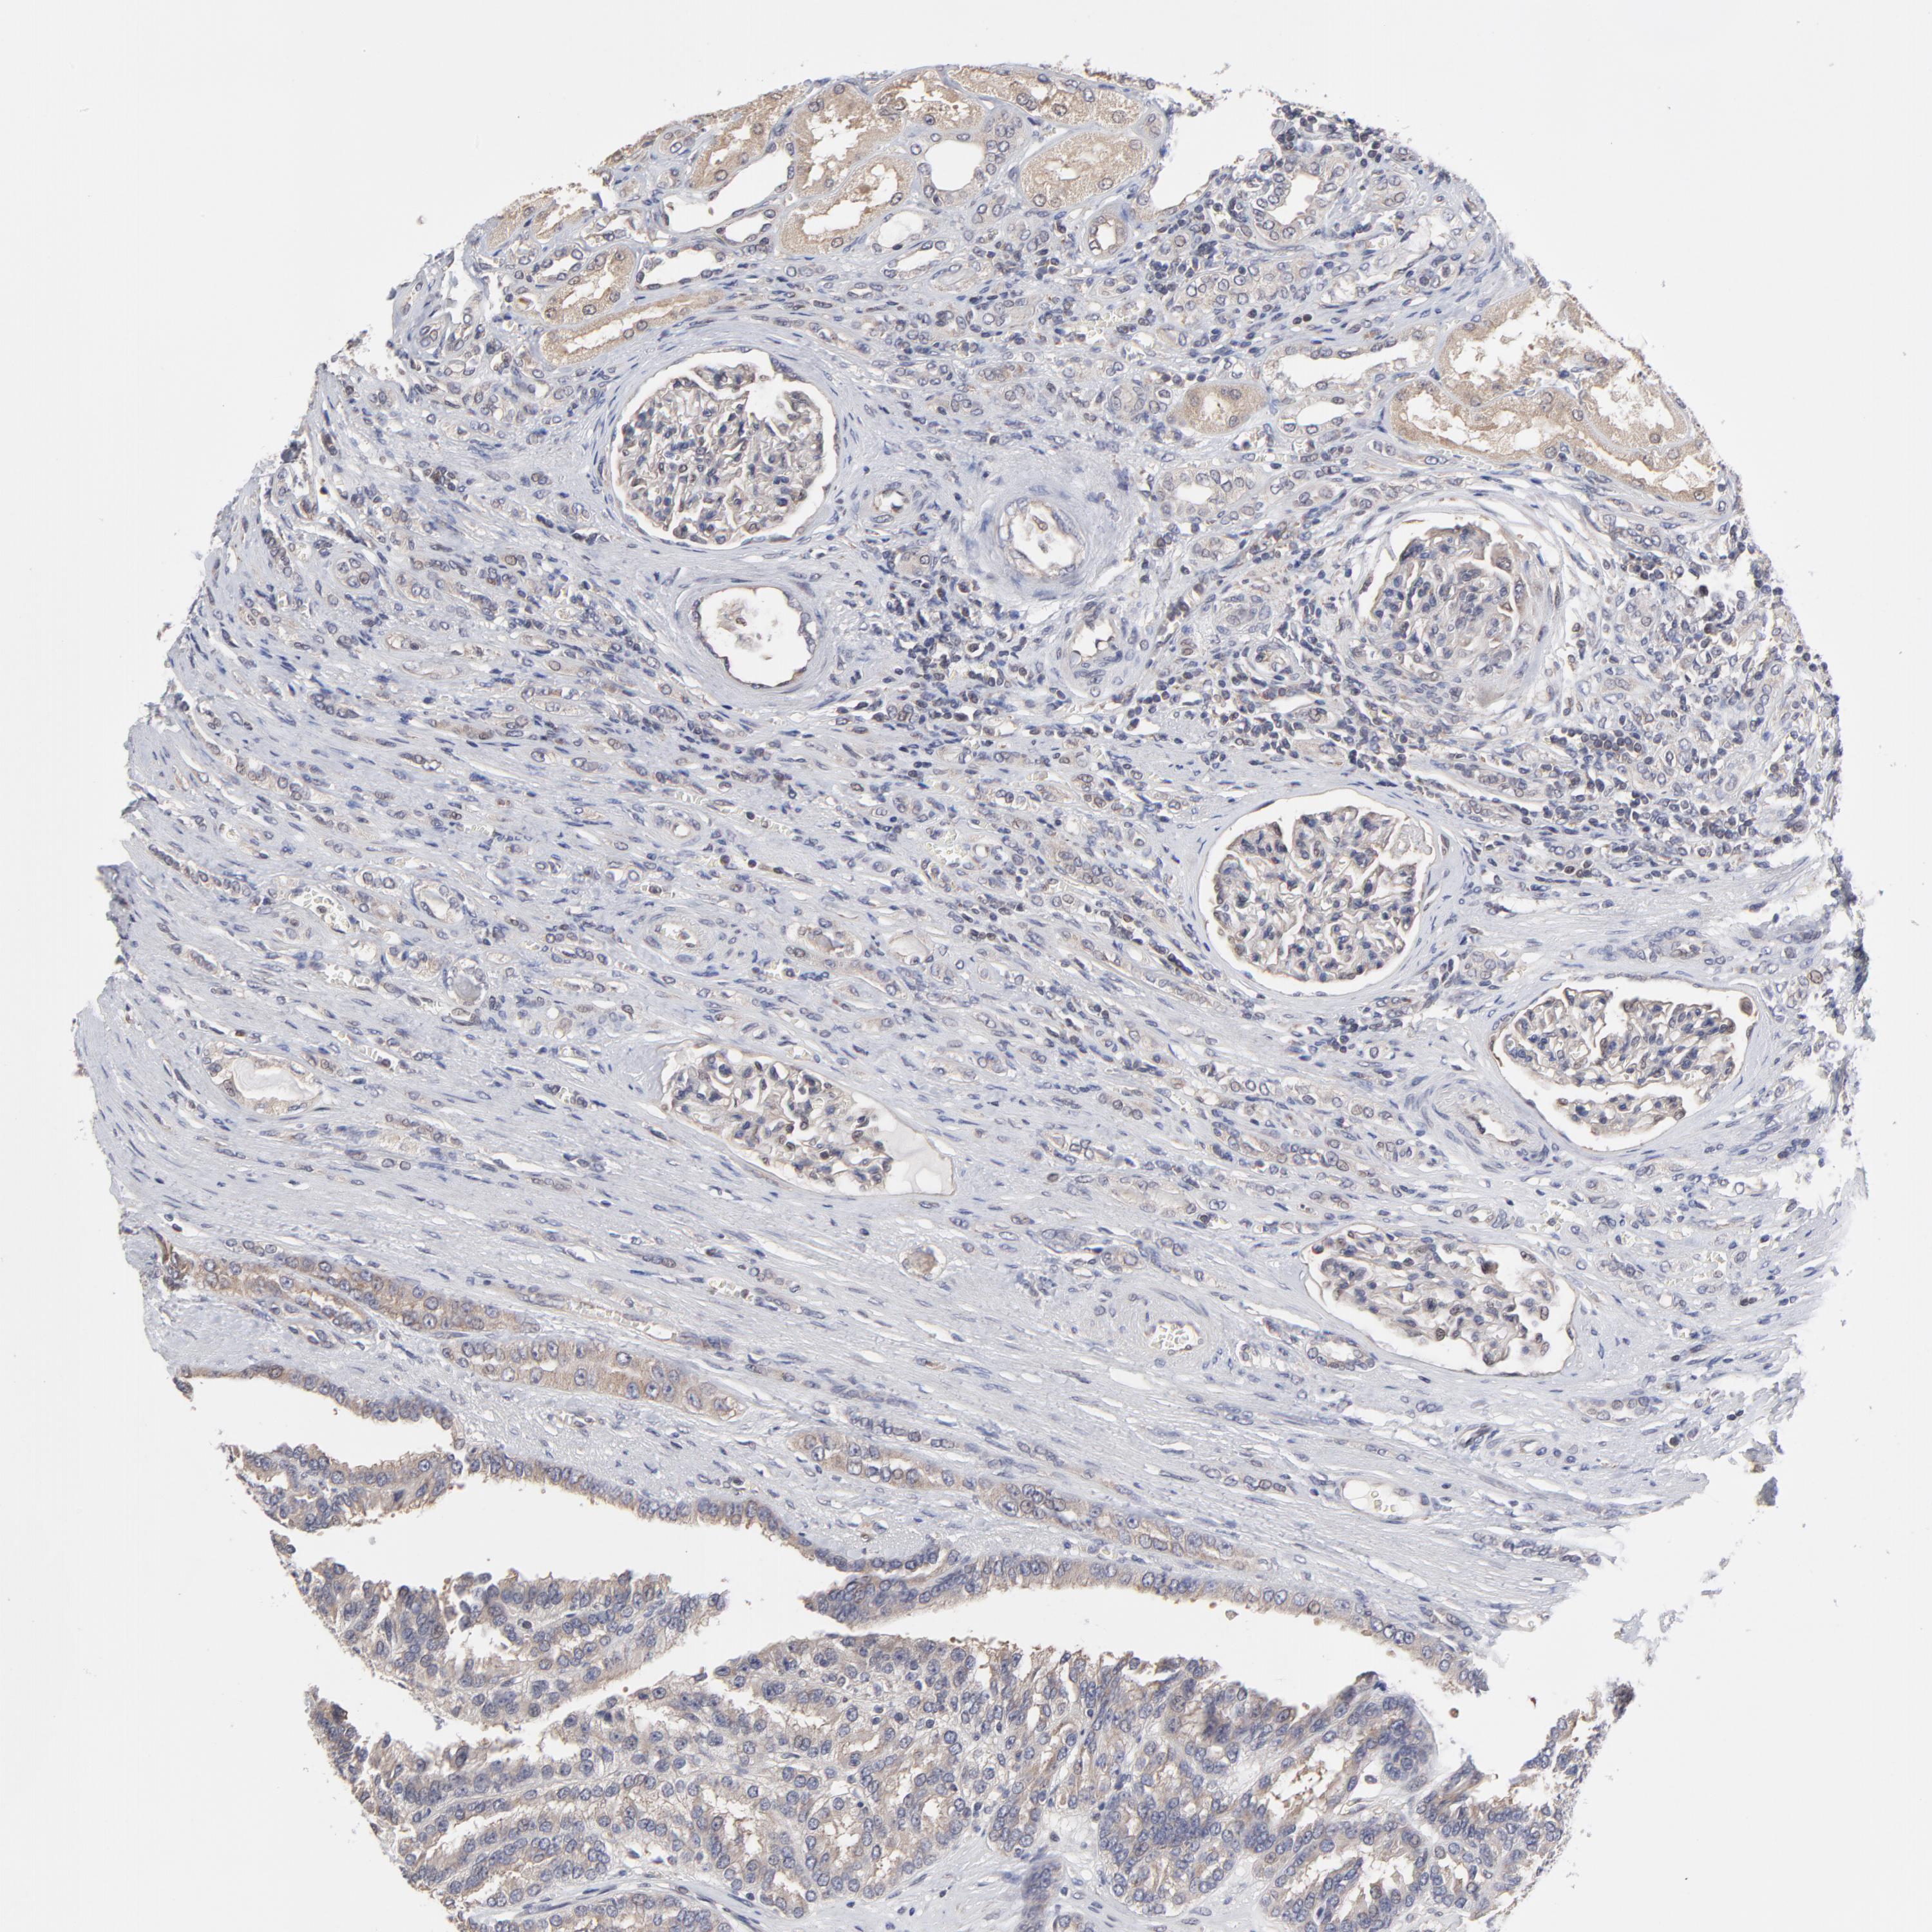

KIDNEY RENAL CLEAR CELL CARCINOMA (VALIDATION) - Interactive survival scatter ploti

The Survival Scatter plot shows the clinical status (i.e. dead or alive) for all individuals in the patient cohort, based on the same data that underlies the corresponding Kaplan-Meier plots. Patients that are alive at last time for follow-up are shown in blue and patients who have died during the study are shown in red.

The x-axis shows the expression levels (FPKM) of the investigated gene in the tumor tissue at the time of diagnosis. The y-axis shows the follow-up time after diagnosis (years). Both axes are complimented with kernel density curves demonstrating the data density over the axes. The top density plot shows the expression levels (FPKM) distribution among dead (red) and alive patients (blue). The right density plot shows the data density of the survived years of dead patients with high and low expression levels respectively, stratified using the cutoff indicated by the vertical dashed line through the Survival Scatter plot. This cutoff is automatically defined based on the FPKM cutoff that minimizes the p-score. The cutoff can be changed by dragging the vertical line or by entering a cutoff value in the square labeled "Current cut-off".

Under the Survival Scatter plot the p-score landscape (black curve; left axis) is shown together with dead median separation (red curve; right axis). Dead median separation is the difference in median mRNA expression between patients who have died with high and low expression, respectively. It is calculated as follows: median FPKM expression of dead patients with high expression - median FPKM expression of dead patients with low expression. This is intended to aid the user in visually exploring custom cutoffs and the associated p-scores and dead median separation.

Individual patient data is displayed and can be filtered by clicking on one or more of the category buttons on the top of the page. Categories describing expression level and patient information include: high, low, alive, dead, female, male and tumor stages. The scale of the x-axis can be toggled between linear and log-scale by clicking on the "x log" button. Mouse-over function shows TCGA ID, patient information and mRNA expression (FPKM) for each patient.

& Survival analysisi

Kaplan-Meier plots summarize results from analysis of correlation between mRNA expression level and patient survival. Patients were divided based on level of expression into one of the two groups "low" (under cut off) or "high" (over cut off). X-axis shows time for survival (years) and y-axis shows the probability of survival, where 1.0 corresponds to 100 percent.

ZNF157 is not prognostic in Kidney Renal Clear Cell Carcinoma (validation)